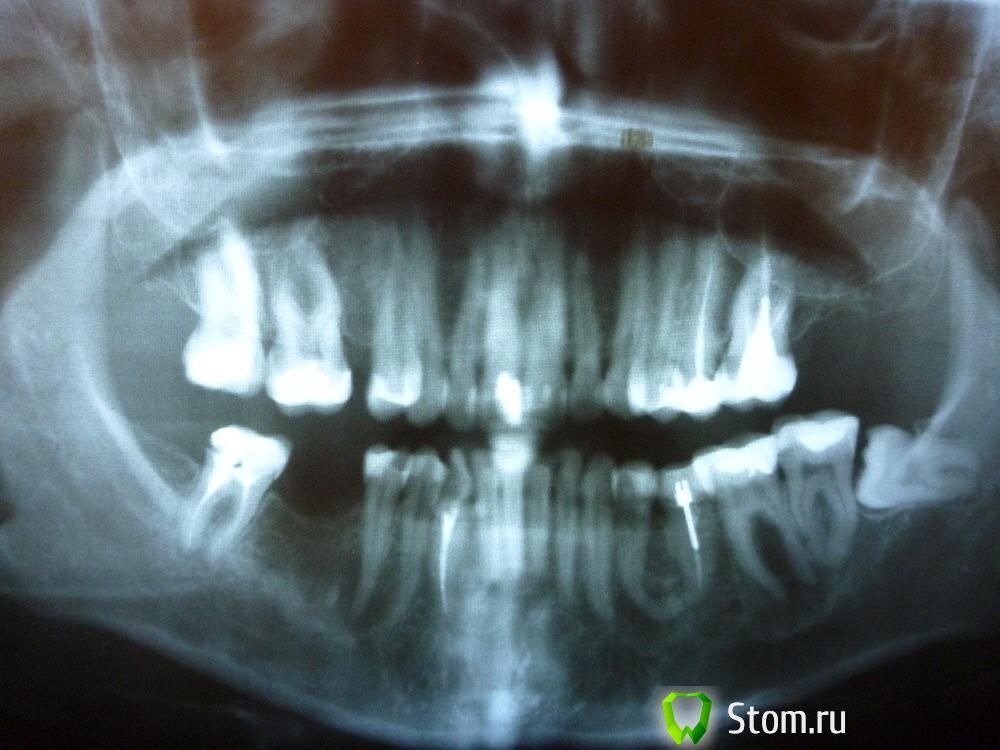

IvanK Опубликовано 25 ноября, 2011 Поделиться Опубликовано 25 ноября, 2011 Коллеги , посоветуйте Ваш план лечения.Пациентка обратилась с целью протезирования. Была направлена на ОПТГ. Обнаружены "кисты".Предположены амелобластома или первичная киста. Направлена на кафедру в 1 мед. Сказали, что "обычные кисты".Вижу 2 варианта:1). эндодонтическое лечение, цистэктомия, гистология, резекция верхушек корней, наблюдение, далее костная пластика?, имплантация. 2) Удаление зубов с периапикальными изменениями + 8-ка, гистология, пластика, имплантация боковых отделов. Ссылка на комментарий

koss Опубликовано 26 ноября, 2011 Поделиться Опубликовано 26 ноября, 2011 34 это полные вилы в плане эндодонтии . но попробовать было бы интересно Ссылка на комментарий

Afffinity Опубликовано 26 ноября, 2011 Поделиться Опубликовано 26 ноября, 2011 ИМХО, 38 и 45 лучше удалить Ссылка на комментарий

Corvalus Опубликовано 26 ноября, 2011 Поделиться Опубликовано 26 ноября, 2011 Эндодонтическое лечение: 45,44,33-го тоже он в зоне кисты,34,36. Хуже дела обстоят с 35-м, глянуть бы прицельный снимок, если периапикальные изменения есть, то шуруп трудно достать будет. Обязательно реэндодонтия 43. Далее цистэктомия без всяких резекций с обязательной гистологией. Заполнять кисты не стал бы, достаточно крови, очаг гнойный. Через несколько недель парадонтологическое лечение, после костная пластика с отсроченной имплантацией. И в конце рациональное протезирование одиночными коронками. При нормальном эндодонтическом лечении рецедива кист не должно быть, а если и будет, то не на всех зубах сразу. Себе зубы удалять не стал бы, опыт лечения таких зубов есть, с имплантацией всегда решить можно по ходу поступления проблем. Второй вариант имеет место быть. Объяснить пациентке все за и против, пусть сама выбирает. Ссылка на комментарий